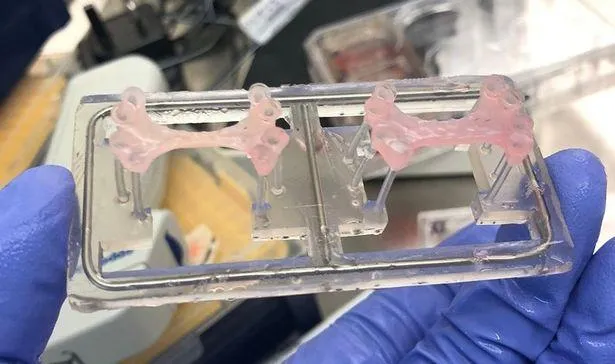

Пластир містить до 50 мільйонів людських стовбурових клітин, які перетворюються на здоровий серцевий м’яз. Розробка містить речовини, які здатні відновлювати та оновлювати клітини серця.

За словами дослідників, пластирі підживлювалися кровоносними судинами, які ростуть від серця реципієнта.